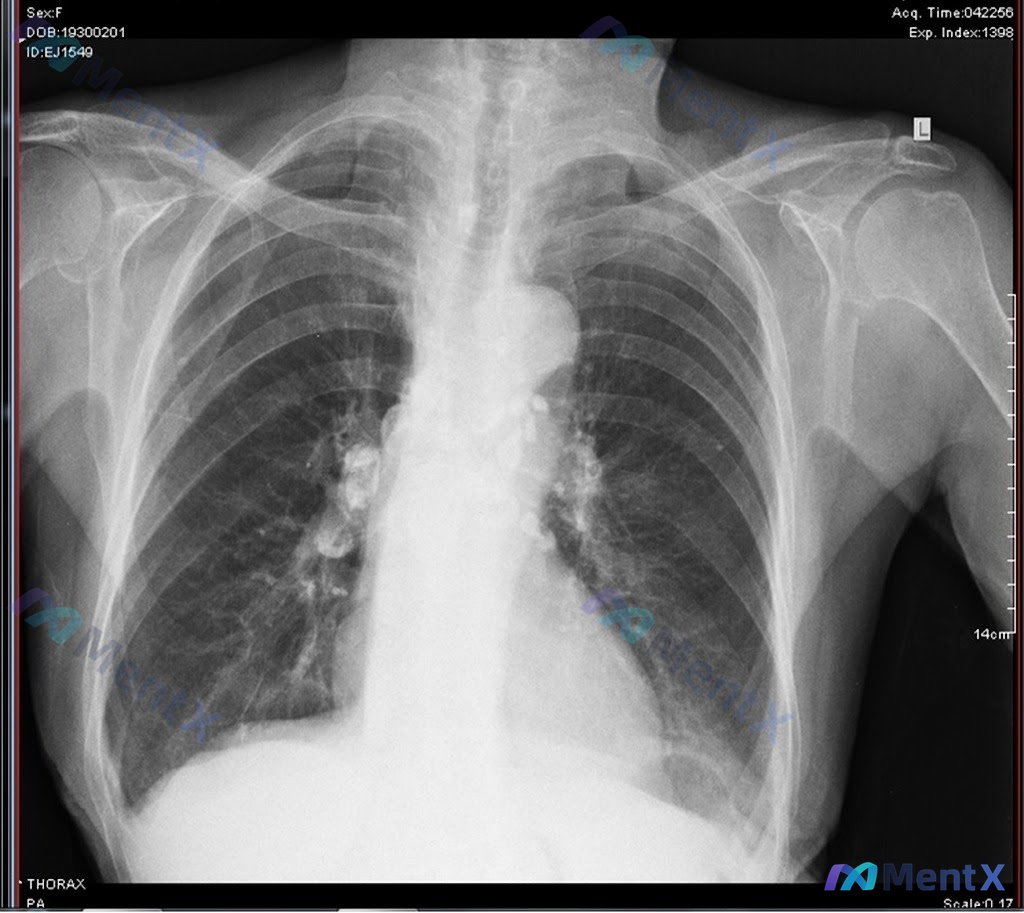

看到这个病例资料,觉得挺有启发的,整理了一下思路和大家分享。 --- 病例核心信息梳理 一般情况:57岁女性,墨西哥出生,有监禁史 主诉:咳嗽加剧、呼吸急促、盗汗 现病史:2个月来无饮食改变但体重意外减轻10磅 既往史/危险因素:高血压、高脂血症;每日吸烟1包;青春期PPD测试阳性 影像检查:胸部正...